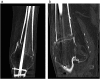

Bone healing is a complex and well-orchestrated physiological process, in which bone repairs and regenerates regaining its original biomechanical and biochemical properties. It is estimated that 5 to 10% of all fractures are complicated by delayed union or non-union. Progression to non-union is thought to be multifactorial, even though the exact biological sequence remains obscure. Treatment should aim to addressing deficiencies in both the mechanical and biological components, along with eliminating co-factors that could negatively affect the locally induced fracture healing response. We report a case of a 78-year-old patient who presented with a distal femoral non-union above a previously fused knee, which was successfully managed with exchange nailing and intramedullary delivery of recombinant human bone morphogenetic protein-7 (rhBMP-7).